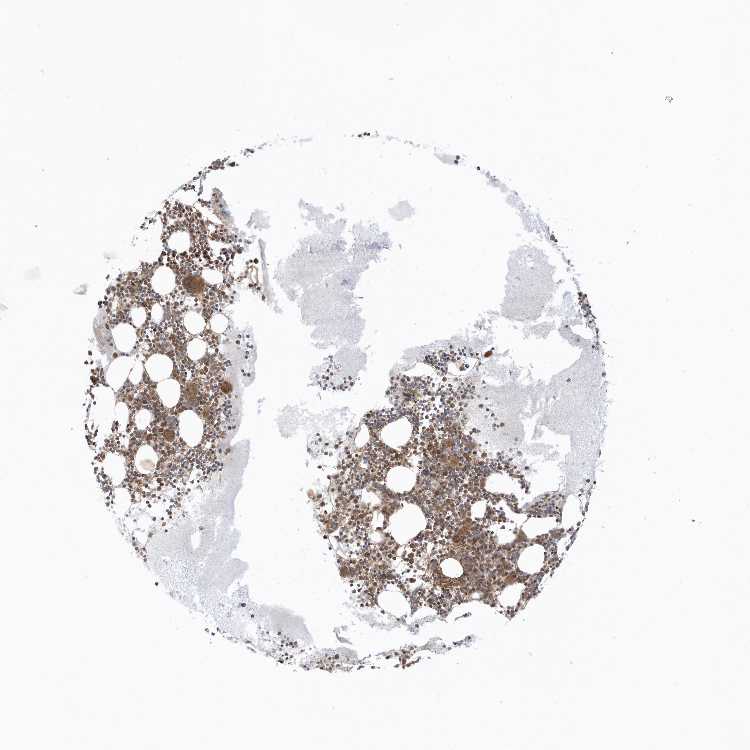

BONE MARROW - Antibody stainingi

Antibody staining in the annotated cell types in the current human tissue is reported as not detected, low, medium, or high, based on conventional immunohistochemistry profiling in selected tissues. This score is based on the combination of the staining intensity and fraction of stained cells.

Each image is clickable and will lead to virtual microscopy that enables deeper exploration of all samples and also displays staining intensity scores, fraction scores and subcellular localization as well as patient and tissue information for each sample.

Antibody HPA035399

Hematopoietic cells Medium